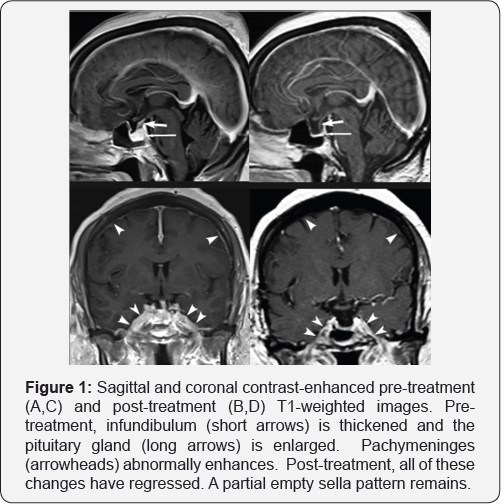

Endocrine tests indicated pan-hypopituitarism: LH 0.2IU/L (reference range in menopause 13.1-86.5), FSH 1.0IU/L (reference range in menopause 21.5-131), free T4 0.35ng/dL (reference range 0.78-2.19), TSH 0.44mU/L (reference range 0.46-4.68), GH 0.2ng/ml (reference range ,10), IGF-1 118ng/ ml (reference range 50-317; -1.4 SD for age), IGF-BP3 2.5mg/L (reference range 3.4-6.9), A.M. cortisol 0.83p.g/dL (reference range 4.5-22.7), and ACTH 6pg/mL (reference range 6-50). The PRL level was increased at 56ng/mL (reference range 3.0-18.6). The plasma osmolality was 290m0sm/kg while the urine osmolality was 236mOsm/kg which rose to 827mOsm/ kg following dDAVP, consistent with central diabetes insipidus. Magnetic Resonance Imaging (MRI) revealed diffuse dural thickening, pituitary enlargement and mild leftward deviation of the pituitary stalk (Figure 1A). The level of angiotensin converting enzyme in serum 40U/L (reference range 9-67) and CSF 4U/L (reference range <15) was normal. Dural biopsy showed both non-caseating and caseating granulomas with focal scanty necrosis. Chest CT was normal. Isolated neurosarcoidosis was diagnosed after extensive testing to exclude infection and malignancy. She was treated with prednisone and methotrexate as well as levothyroxine and desmopressin. A repeat MRI after 8 months revealed partial resolution of the dura thickening and an empty sella (Figure 1).

Sarcoidosis is a multisystem inflammatory disorder that is defined by the histological finding of noncaseating granulomas. While the disorder can affect any organ, the lung, liver, eye and skin are most commonly involved. The nervous system is affected in 5-14% of cases, which may occur in isolation [7]. Patients with neurosarcoidosis may present with partial or complete anterior hypopituitarism, diabetes insipidus (DI), and hyperprolactinemia [8]. Excess thirst and polyuria may also occur without DI [9]. The diagnosis of isolated neurosarcoidosis can be challenging, as it can present with a wide variety of symptoms and imaging findings [9,10]. Involvement of the leptomeninges can be diffuse, focal or multifocal. The brain parenchyma and spinal cord may be affected, and in some cases the MRI appears normal. Basilar leptomeningeal disease can involve the cranial nerves and the hypothalamus-pituitary unit where the differential diagnosis includes lymphocytic hypophysitis, histiocytosis, tuberculosis, leukemia and metastasis. Measurement of the angiotensin converting enzyme level in serum and CSF is rarely helpful [11], and biopsy is needed for definitive diagnosis. Neurosarcoidosis patients are generally treated with high dose corticosteroids and immunosuppressive agents, and while the neurosarcoid lesions may regress, endocrine dysfunction is usually irreversible [8]. This case demonstrates that empty sella can be the direct outcome of sarcoidosis affecting the pituitary